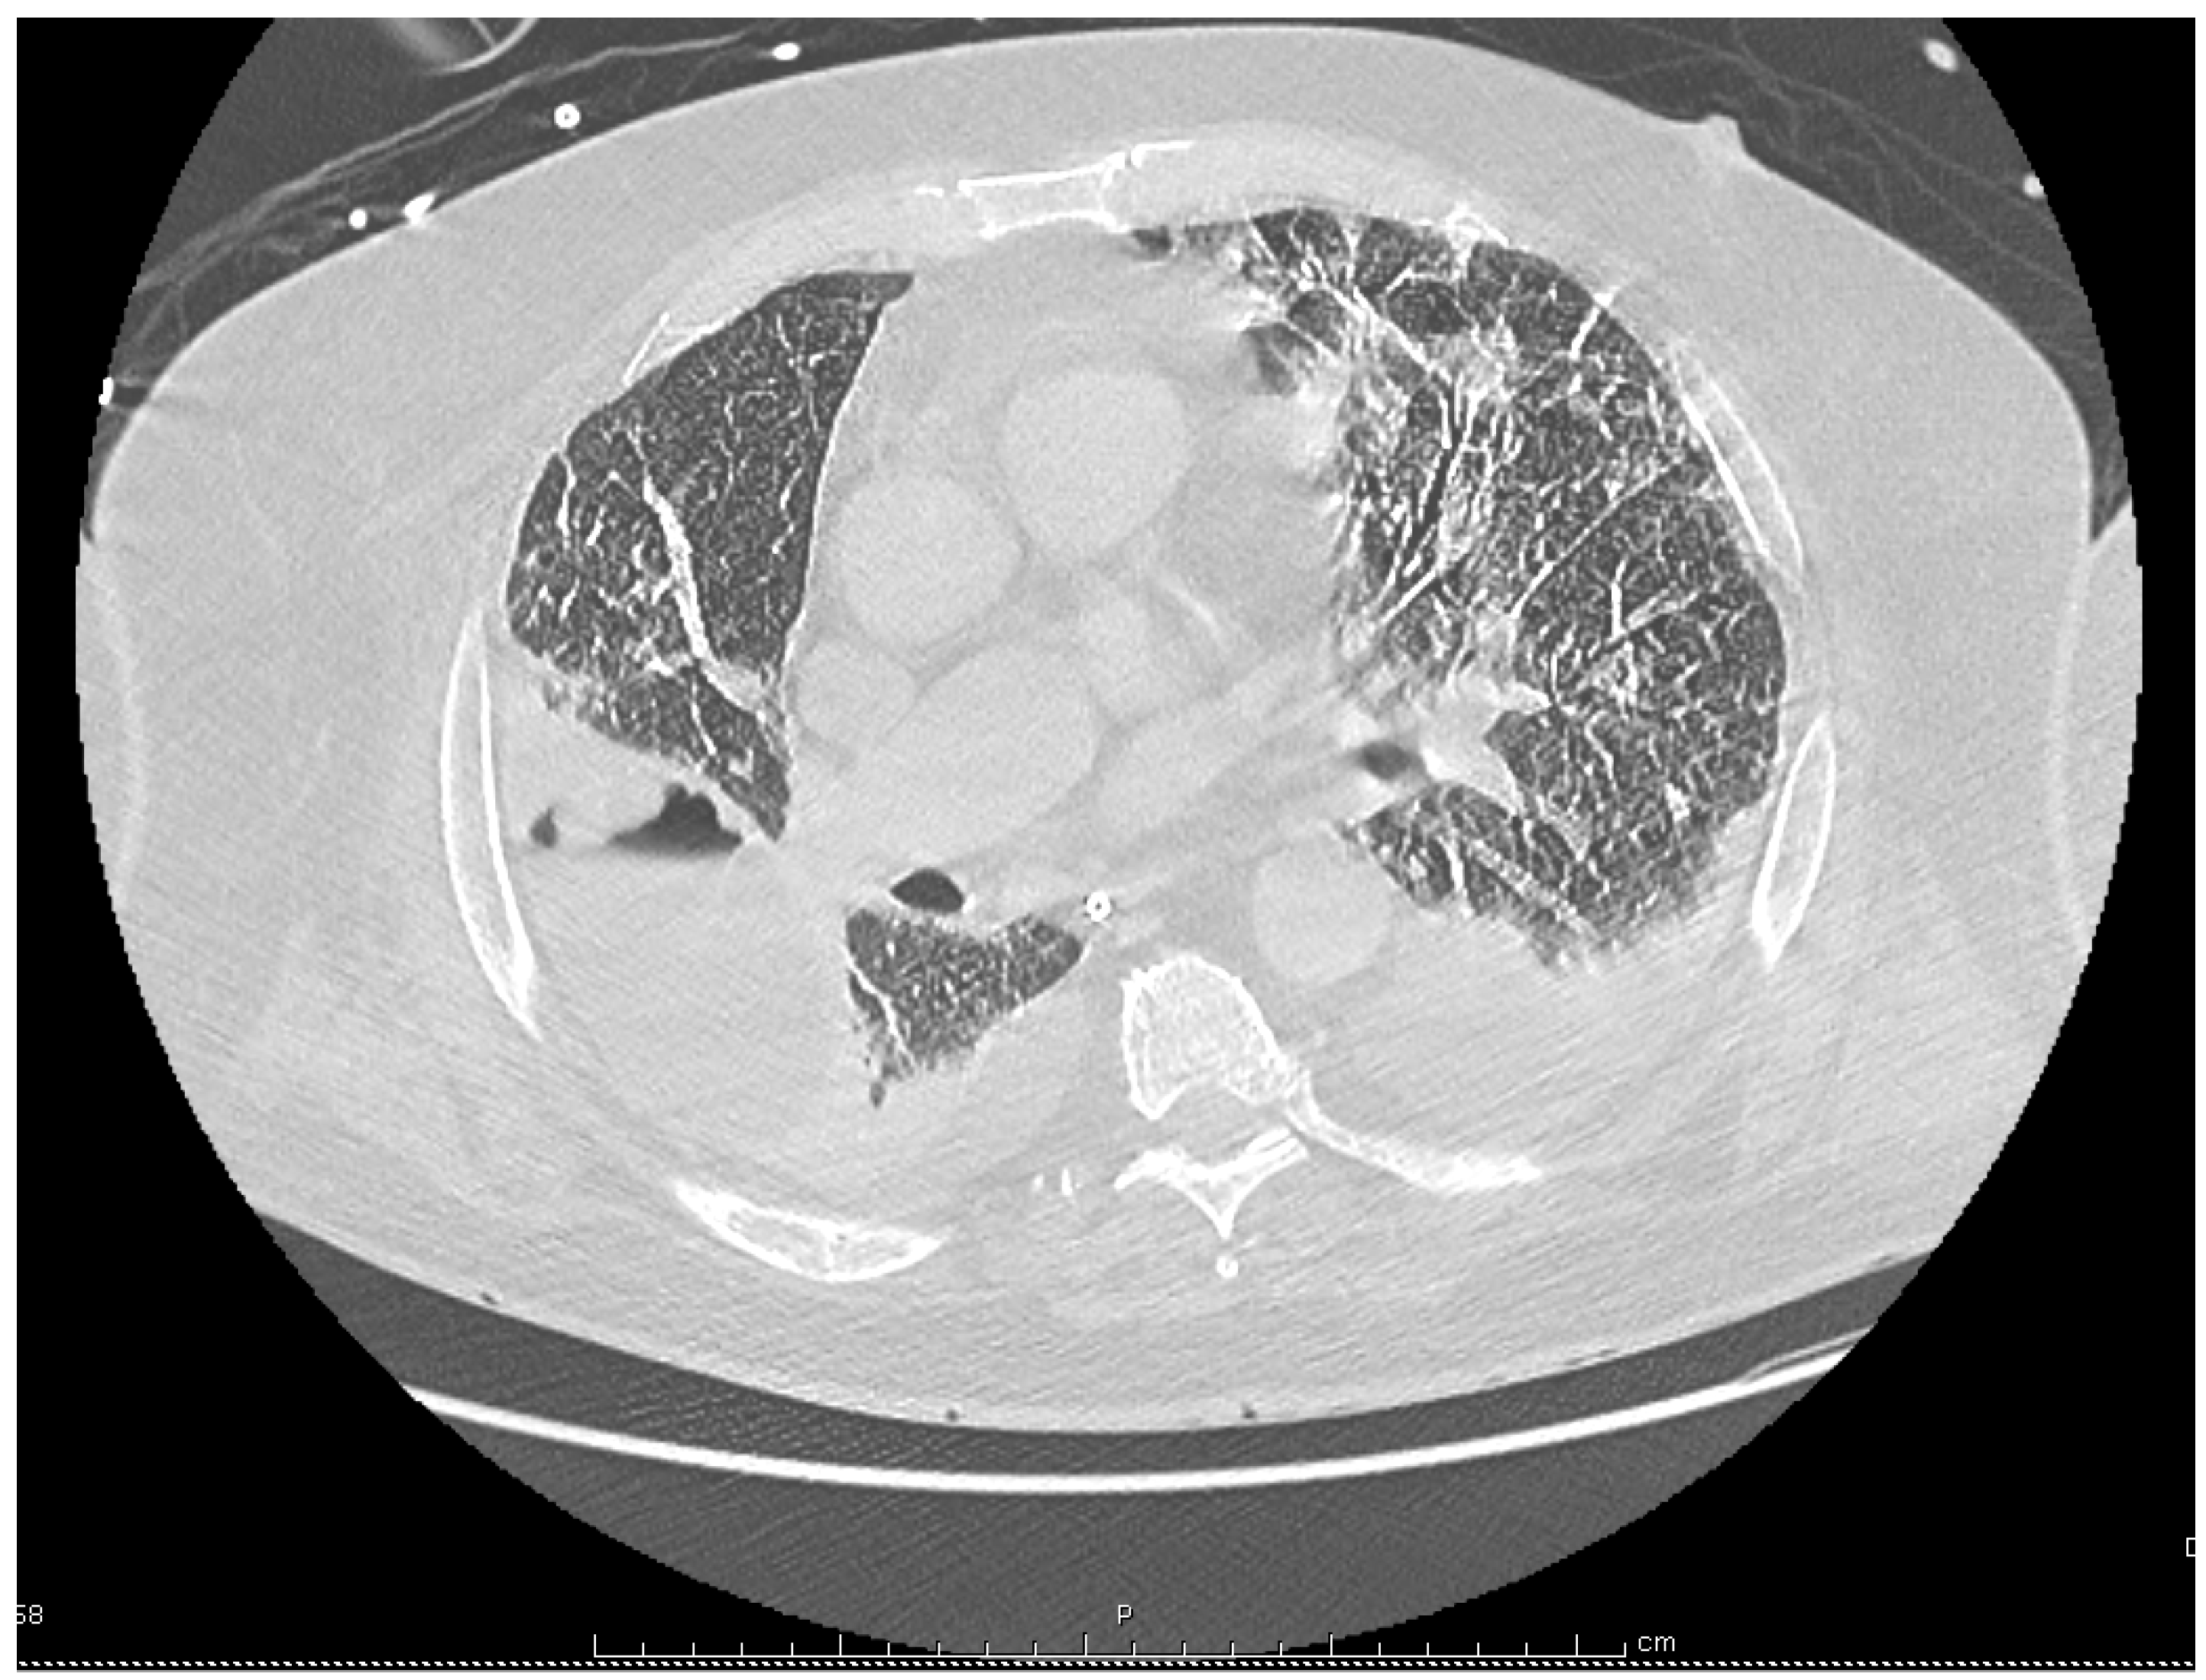

Despite these treatments the patient’s condition deteriorated with the onset of respiratory failure and septic shock, requiring the use of vasoactive drugs and mechanical ventilation. Antimicrobial coverage was therefore broadened with the replacement of cefotaxime and levofloxacin by i.v. meropenem, 2 g every 8 h, and i.v. linezolid 600 mg twice a day, although no pathogenic bacteria had been identified yet. A chest computed tomography (CT) showed bilateral pleural effusions, patchy alveolar infiltrates, and a large abscess in the right lobe measuring 85 by 57 by 53 mm (Figure 2). Intravenous voriconazole 400 mg every 12 h, was thus substituted for fluconazole with concern for an Aspergillus infection, and acyclovir was discontinued.

Figure 2.

Chest computed tomography performed on the 21st day of hospitalization, showing bilateral pleural effusions, and the occurrence of a large abscess in the right lung.